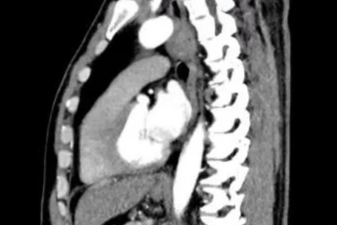

吃饭喝水全漏进肺里,他自己却浑然不知!